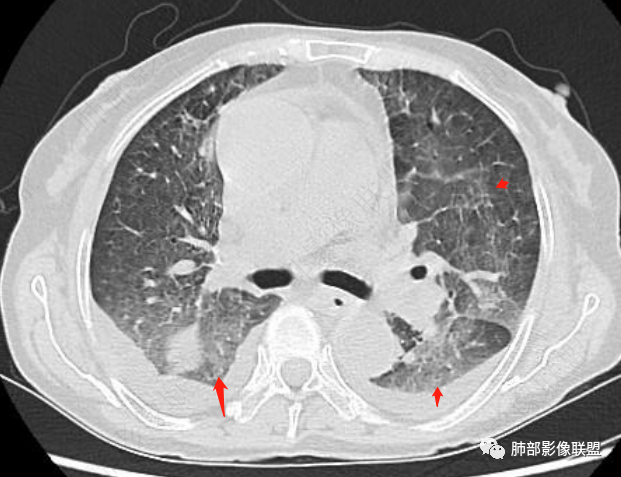

片状磨玻璃影,多发结节,类风湿肺炎?

发热,有类风湿性关节炎、糖尿病基础病,长期口服激素及免疫抑制剂,双肺多发磨玻璃影及小叶间隔增厚,蜂窝影,支气管扩张考虑非特异性间质性肺炎存在,左肺上叶不规则结节影,周围长毛刺局部肺气肿,考虑慢性炎症,结合pct及crp升高考虑细菌感染,另真菌g升高考虑结合宿主因素,真菌感染需要积极排除。

老年,外阴溃疡加发热,感染指标明显有异常,血气分析,过度呼吸及低氧血症,宿主因素,糖尿病和激素,基础疾病RA。影像,双下肺体积有缩小,有蜂窝?双肺磨玻璃,多发结节,双侧胸水。树芽不明确。是否有旧片,这个患者有UIP背景,是否感染或者UIP急性加重,或者基础上合并肺栓塞及肺水肿?长期激素,没有提供CD4细胞亚群,存在2种情况,1,风湿病没有压制住,肺考虑CTD相关性间质改变,压制过猛,结合感染指标,奴卡是有可能的。激素加糖尿病,结核也带排,激素加磨玻璃加G实验阳性,PCP也带排,临床信息太少,进一步排查

老年女性,外阴溃疡伴发热,有类风、糖尿病病史,血象及炎症指标高,G试验升高;影像:磨玻璃密度(中央分布为主)胸膜下蜂窝状改变心影增大、两侧胸腔少量积液;小叶间隔增厚,结节;考虑:1.中央分布为主的GGO需考虑:肺水肿、出血、PJP、肺泡蛋白沉着症;2.胸膜下间质性改变蜂窝肺,需考虑UIP、CTD-ILD,综合:两元论:CTD-ILD奴卡,或肺水肿

①影像表现复杂:较弥漫间质性改变,对称磨玻璃密度为主,小叶间隔增厚,有一定重力分布趋势,未见明显纤维化,气囊及蜂窝位于肺边缘,未见典型“月弓征”。心脏影增大,双侧胸腔积液。

这即可见于间质性肺病,也可见于真菌感染(如PJP)、病毒感染,类风湿,以及肺水肿等等。

一般而言,如存在磨玻璃密度影浑浊,有重力分布趋势,肺表面蜂窝影,胸腔积液等等,并不常见于单纯PJP,除非其他因素叠加。